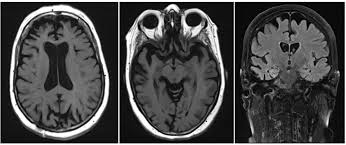

Lewy, the scientist who discovered them. Loss of substantia nigra hyperintensity on 7 tesla mri of parkinson's disease, multiple system atrophy, and progressive supranuclear palsy. Besides nuclear imaging methods, the clinical utility of structural neuroimaging with magnetic resonance imaging (mri) for differential comparison between dementia with lewy bodies and alzheimer's disease. You also might see things that aren't there, called hallucinations. Lbd is a term that covers two conditions that have similar. Protein deposits, called lewy bodies, develop in nerve cells in the brain regions involved in thinking, memory and movement (motor control). Certain nuclear scans of the brain, including positron emission. How is lewy body dementia (ldb) diagnosed? Dr michael firbank discusses his study using functional mri in lewy body dementia and alzheimer's disease at the newcastle university institute. Focal atrophy in dementia with lewy bodies on mri: Memory loss is not always an early symptom. Lewy body dementia (lbd) is a type of progressive dementia. Many people also experience changes in alertness including daytime sleepiness, confusion or staring spells.

Lewy, the scientist who discovered them. These deposits, called lewy bodies, affect chemicals in the brain whose changes, in turn, can lead to problems with thinking, movement, behavior, and mood. Many people also experience changes in alertness including daytime sleepiness, confusion or staring spells. Mri can show loss of brain cells (atrophy), but this occurs with other types of dementia too. Lewy body dementia stage 2 possibilities.

By this point, most caregivers are worried that something is seriously wrong and seek medical attention. These deposits, called lewy bodies, affect chemicals in the brain whose changes, in turn, can lead to problems with thinking, movement, behavior, and mood. Many people also experience changes in alertness including daytime sleepiness, confusion or staring spells. In lbd, protein deposits build up in the brain. Lewy body dementia (lbd) is a type of progressive dementia that leads to a decline in thinking, reasoning and independent function because. Dementia with lewy bodies or lewy body dementia is dementia caused by the presence of lewy bodies in the brain. Lewy body dementia (lbd) is often regarded as the second most common dementia in older individuals after alzheimer disease,1,2 possibly sharing the. Memory loss is not always an early symptom. How is lewy body dementia (ldb) diagnosed? Lewy body dementia symptoms include recent loss of memory, difficulty concentrating or paying attention, misperceptions of space and time. The deposits are called lewy bodies and are named after friedrich h. Mri can show loss of brain cells (atrophy), but this occurs with other types of dementia too. Protein deposits, called lewy bodies, develop in nerve cells in the brain regions involved in thinking, memory and movement (motor control).

Protein deposits, called lewy bodies, develop in nerve cells in the brain regions involved in thinking, memory and movement (motor control). It's rare in people under 65. Also, there is a helpline for support provided by dementia. Dementia with lewy bodies (dlb), also known as lewy body disease, is a neurodegenerative disease (a synucleinopathy to be specific) related to parkinson disease. Dementia with lewy bodies appears to be the second most common form of dementia, accounting for about one in five cases. Further research is needed to clarify the relationships among them. Some scans (ct and mri scans) look at how the different parts of the brain fit together, rather than how the parts work together. The deposits are called lewy bodies and are named after friedrich h. Dementia is the name for problems with mental abilities caused by gradual changes and damage in the brain. Lewy body dementia, also known as dementia with lewy bodies, is the second most common type of progressive dementia after alzheimer's disease dementia. Certain nuclear scans of the brain, including positron emission. This may include a magnetic resonance imaging (mri) or computed tomography (ct) scan of the brain. After alzheimer disease (ad), dementia with lewy bodies (dlb) is one of the most common types of degenerative dementia.